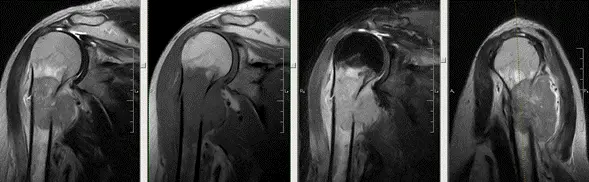

МРТ плечового суглоба

Разом з тим, МРТ діагностика плечового суглоба є останнім і вкрай важливим етапом у виборі тактики лікування. Наприклад, навіть у молодих людей можливі вельми своєрідні знахідки, які кардинально змінюють уявлення лікаря про характер патології і змушують його змінити підходи до лікування.

На знімку приведена картина МРТ плечового суглоба (Київ, діагностичний Центр «Меддіагностика») у 16 річної пацієнтки, яка тривалий час скаржилася на біль в плечовому суглобі. І тільки МРТ дозволило виявити грізне захворювання плечової кістки – пухлина.